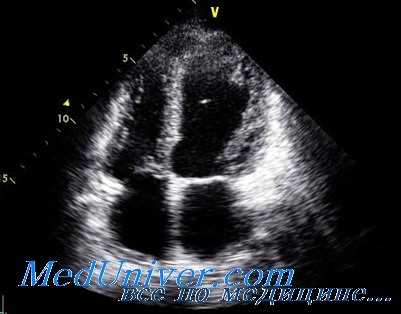

Данные Эхо-КГ: ЛП — 5,1 х 5,7 см; ПП — 3,3 х 4,2 см; конечно-диастолический размер (КДР) ЛЖ — 5,6 см; МЖП — 1,0 см; ФВ — 39,8 %; акинезия всех верхушечных сегментов ЛЖ, гипокинезия средних передне-перегородного, передне-бокового и переднего сегментов; гиперкинезия базальных сегментов; систолическое давление (СД) в ЛА — 76 мм.рт.ст. (N — 30 мм.рт.ст.) (рис. 3).

Рис. 3. Эхо-КГ у больной с синдромом такоцубо в первые часы от начала заболевания